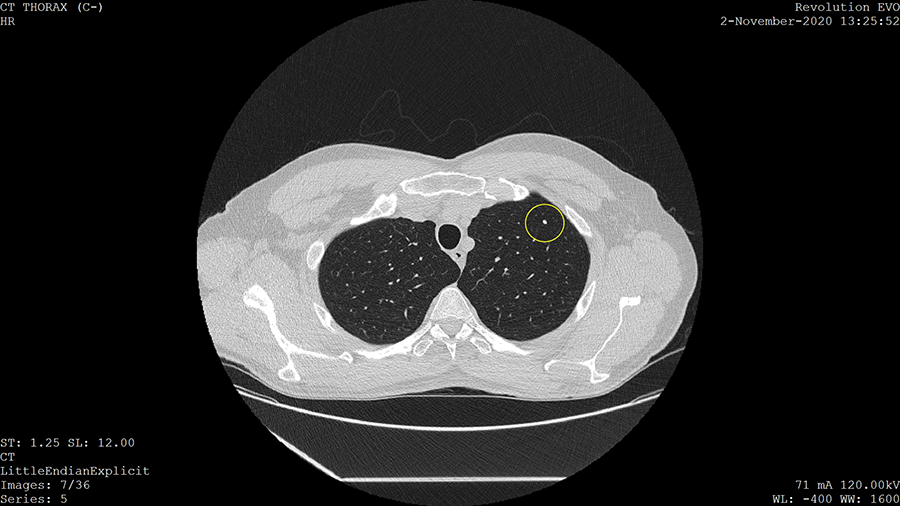

The figure below shows an image produced by LDCT. The bright spot enclosed in a circle is a calcified lung nodule. While these are often benign, they can sometimes be more serious (Khan et al., 2010).

This LDCT image shows a small, bright spot indicated with a circle. This spot is a calcified nodule.